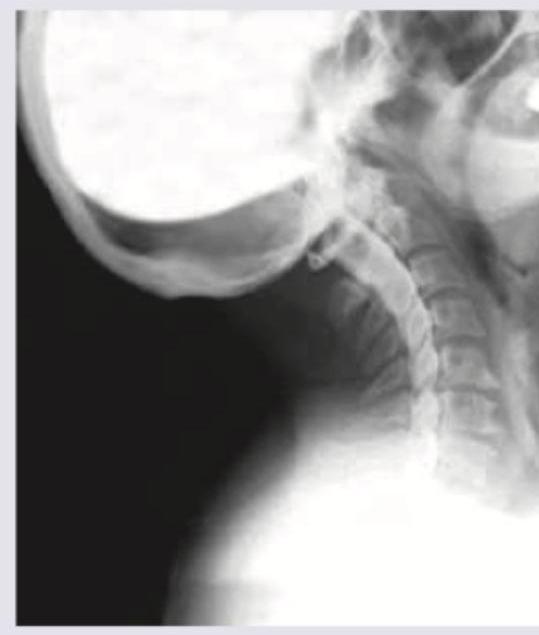

Question 2: Identify the type of investigation shown in the image below.

- B. Myelography (Correct Answer)

Explanation: ***Correct: Myelography*** - The image displays **contrast agent within the spinal canal**, outlining the spinal cord and nerve roots against the bony structures of the cervical spine - This technique is used to visualize **nerve impingement, disc herniation, or spinal cord compression** - Characteristic finding: contrast delineating the thecal sac and nerve root sleeves *Incorrect: Angiography* - Angiography involves injecting contrast into **blood vessels** to visualize vascular structures, detect blockages, or aneurysms - The image shows the **spinal canal** rather than the vascular tree *Incorrect: Neurography* - Neurography (MR neurography) is a specialized **MRI technique** to visualize peripheral nerves themselves - Does not involve injection of contrast into the spinal canal as shown in the image *Incorrect: Fluoroscopy* - Fluoroscopy is a **real-time X-ray imaging technique** used for dynamic assessment or procedure guidance - While fluoroscopy may be used **during** myelography to guide needle placement, the specific technique of contrast visualization in the spinal canal defines this as myelography